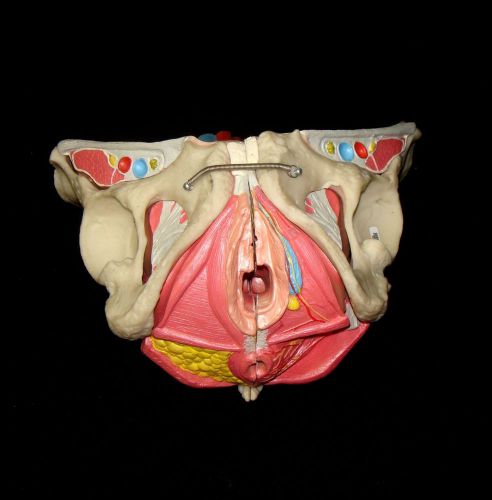

Medical Plastics Laboratory - Female Uterus, Pelvis Anatomical Pelvic Model